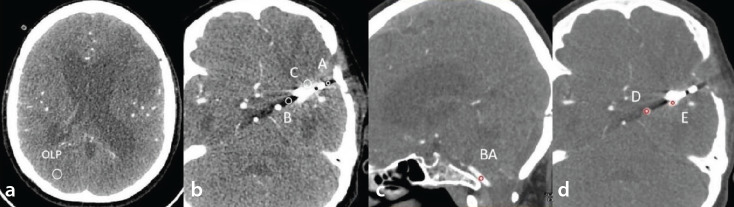

Methods: Sixty patients who underwent DECTA after cerebral aneurysm clipping were analyzed retrospectively. Conventional computed tomography angiography (CTA) was compared with VMIs at 60, 70, 80, 90, and 100 keV. The mean attenuation and standard deviation values within the regions of interest placed in the brain parenchyma and arteries with the worst artifact were measured, respectively. The ΔCT and artifact index (AI) values were calculated to assess the artifact severity. The contrast-to-noise ratio (CNR) was calculated to assess vascular contrast. Two radiologists assessed brain parenchyma and cerebrovascular scores qualitatively using a five-point Likert scale.

Results: Quantitative analysis showed that the artifacts of VMIs were significantly reduced compared with conventional CTA (P ≤ 0.014), except for the ΔCT and AI of 60 keV and the ΔCT of 70 keV. However, there was no significant difference in the vascular contrast on VMIs compared with conventional CTA, except for the CNR of 60 keV (P = 0.008). In qualitative analysis, the proportions of brain parenchyma scores and cerebrovascular scores ≥4 on the VMIs of 70 and 80 keV were higher than those of conventional CTA and other VMIs.

Conclusion: For the patients who underwent DECTA after cerebral aneurysm clipping, the 70-80 keV VMIs are expected to be the optimal energy range for balancing clip artifacts and visibility of adjacent vessels.